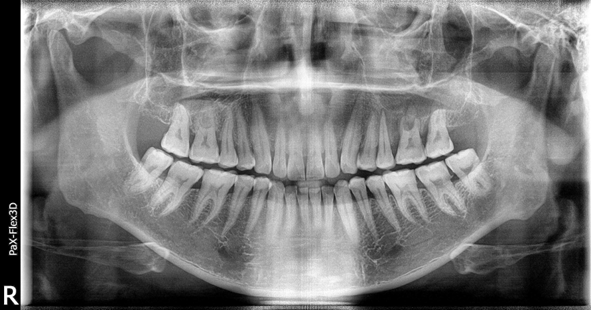

49세 남성

왼쪽 위 어금니 임플란트 식립

(전) 2021-12-28 (후) 2022-08-06

치아 뿌리에 심한 염증으로 치아 뿌리 끝에서 물혹이 발생한 질환(치근낭)이 관찰되어 치근낭적출술 후 뼈이식 진행한 환자분입니다.

발치 후 즉시 식립이 어려워 당일에 뼈이식까지 진행하고 3개월 후 지연식립을 진행했습니다.

치아 뿌리에 생긴 염증이 커지면 잇몸이 붓거나 잇몸뼈가 녹아 치아가 흔들리게 만들 수 있어 빠른 진단과 처치가 필요합니다.